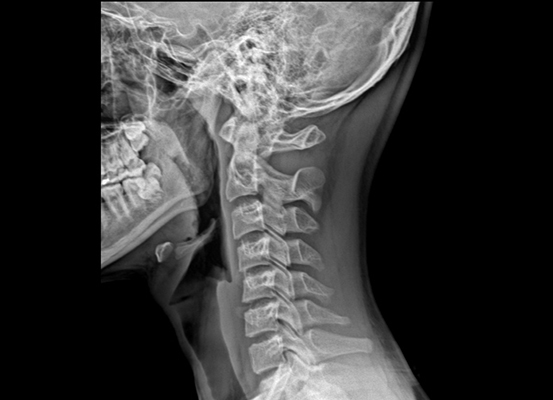

목디스크란 목뼈 사이에 있는 디스크가 손상되어 신경을 압박하는 질환을 의미합니다. 디스크는 젤리와 같은 수핵과 섬유륜으로 구성되어 있습니다. 섬유륜이 손상되면 수핵이 밖으로 밀려나와 신경을 압박하게 됩니다.

목디스크는 주로 잘못된 자세, 과도한 스트레스, 외상 등으로 발생합니다. 잘못된 자세로 장시간 컴퓨터를 사용하거나 운전을 하면 목에 무리가 가고 디스크가 손상될 수 있습니다.

또한 과도한 스트레스는 근육을 긴장시켜 디스크에 손상을 줄 수 있습니다. 외상은 교통사고, 운동 중 충격 등으로 목뼈가 부러지거나 골절되면 디스크가 손상될 수 있습니다.